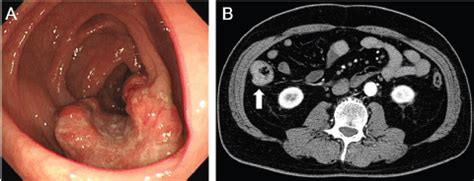

Colon polyp, CT scan - Stock Image C023/4566 - Science ... from www.sciencephoto.com Colon cancer and rectal cancer, collectively known as colorectal cancer, have many similar characteristics and will be discussed as one cancer type in this section. Colon cancer occurs when cells in that vital organ mutate and grow out of control. Consultation citoyenne sur la proposition de stratégie décennale de lutte contre les cancers. Colon cancer develops when tumorous growths develop in the large intestine. Colonoscopy*virtual colonoscopy*sigmoidoscopy*lower gastrointestinal series*tomografie computerizată*imagistică prin rezonanță magneticătomografie cu emisie de pozitroni*test ras. Imagine endoscopică a cancerului colorectal. Concertation citoyenne sur le dépistage du cancer du sein. Bowel (colorectal) cancer is common.

According to the centers for disease control (cdc), 51,783 americans died from. El cáncer colorectal corresponde a una enfermedad producida por un tumor maligno ubicado en la el diagnóstico específico de cáncer colorectal se realiza sólo a través de un estudio histológico. Imagine endoscopică a cancerului colorectal. Colorectal cancer almost always develops from precancerous polyps (abnormal growths) in the screening tests can find precancerous polyps, so that they can be removed before they turn into. Six alternative colon cancer tests: